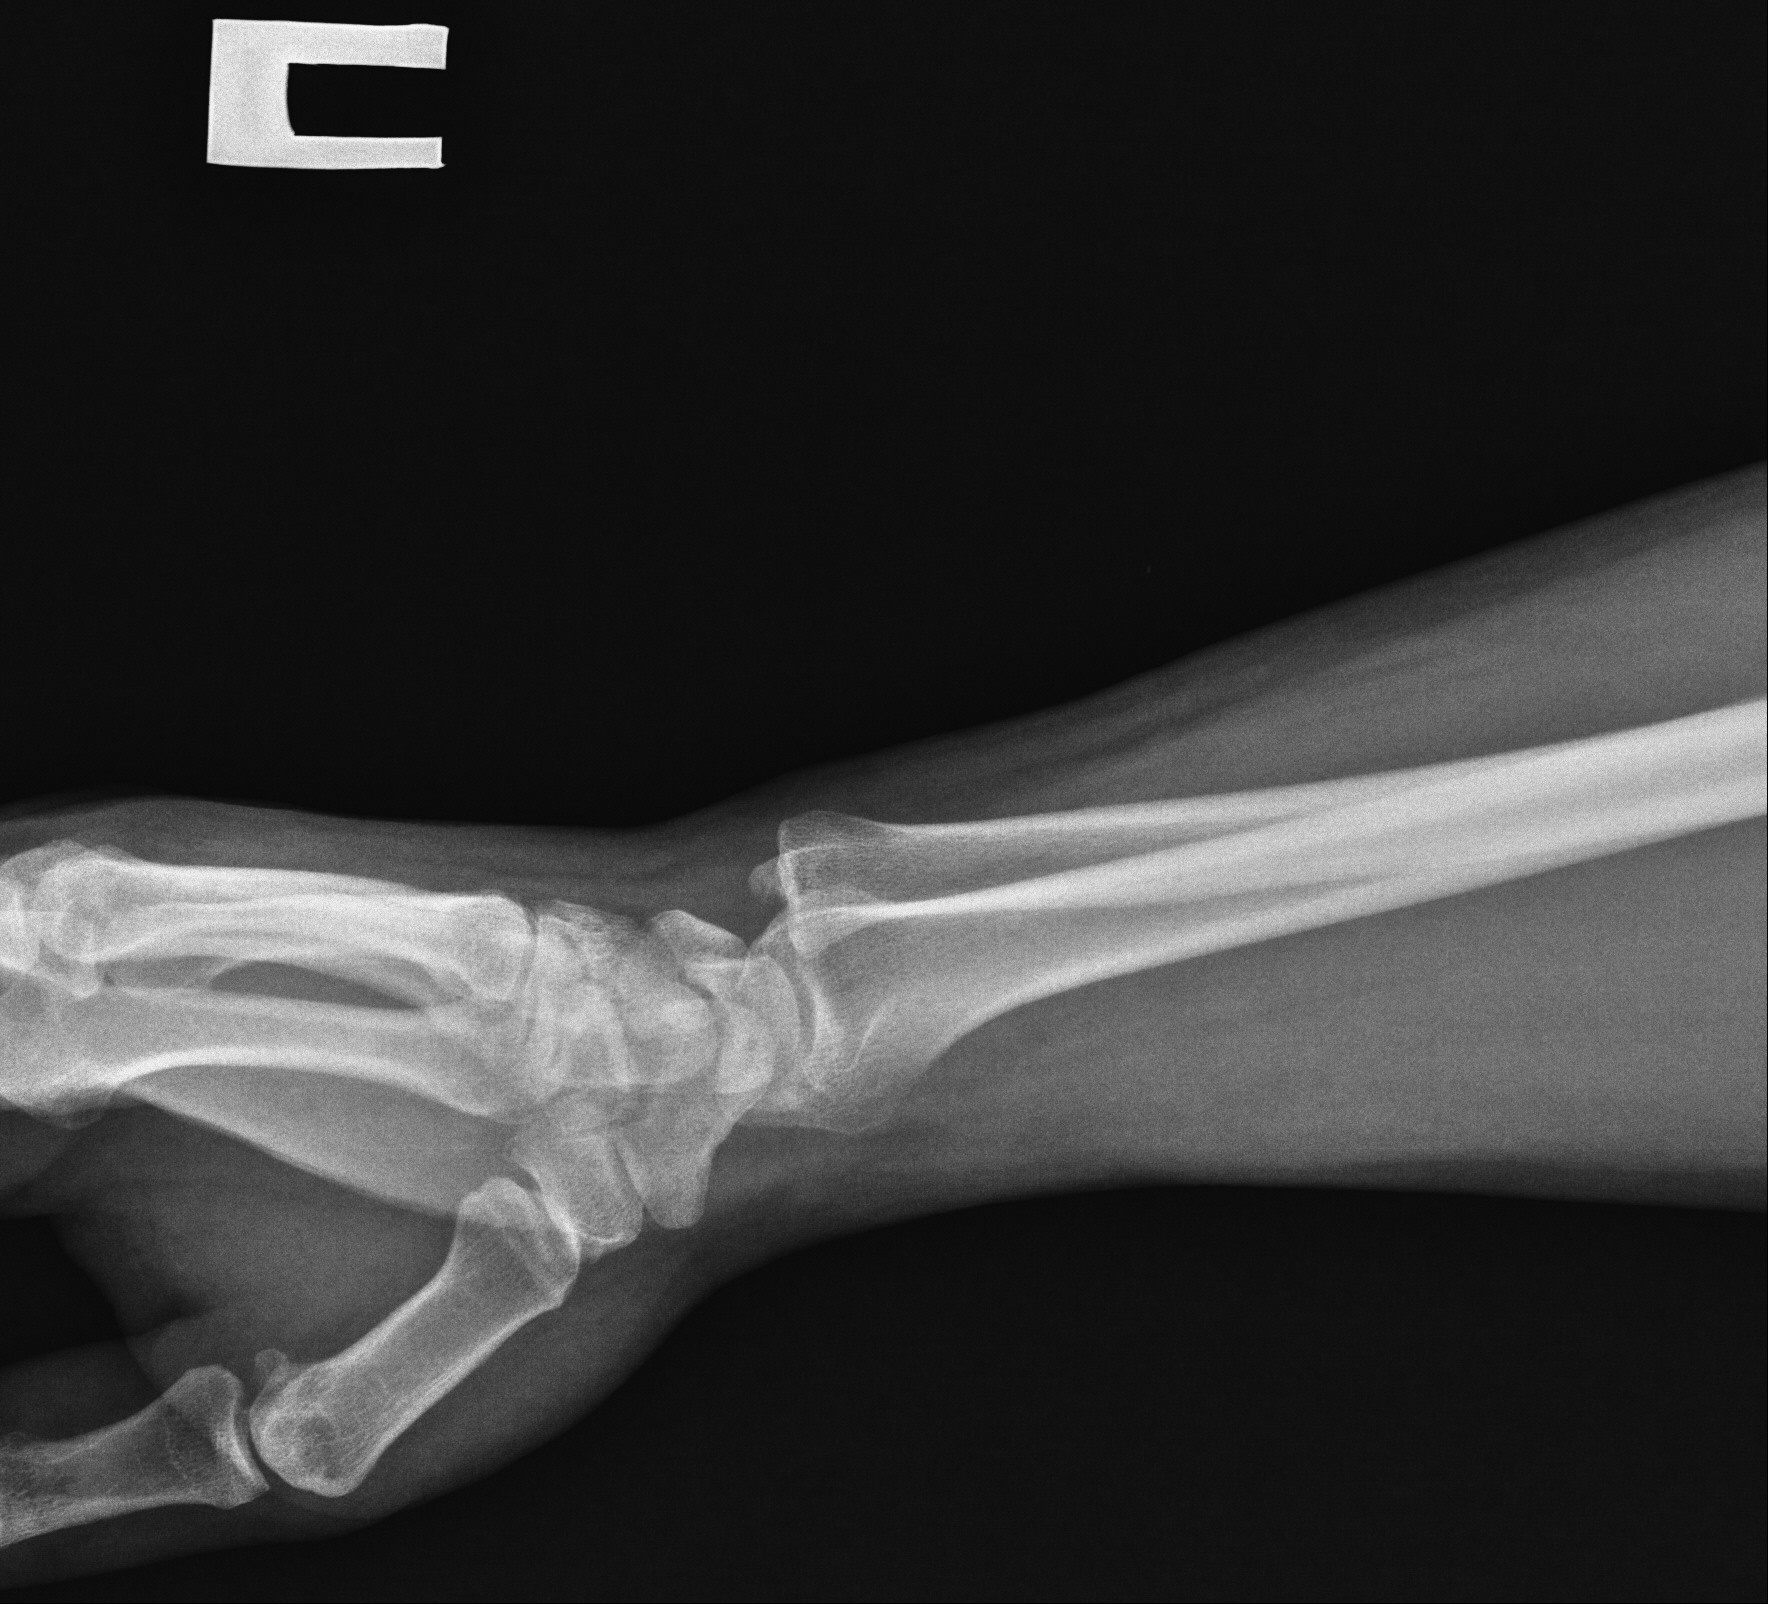

Радиоульнарный угол: строение и особенности лучевой кости